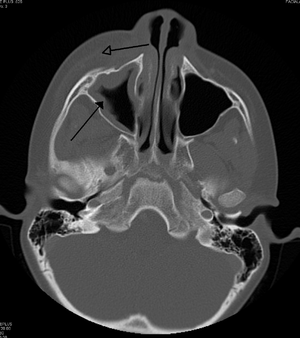

Sinusitis can be caused by infection, allergies, air pollution, or structural problems in the nose. Most cases are caused by a viral infection.[2] A bacterial infection may be present if symptoms last more than ten days or if a person worsens after starting to improve. Recurrent episodes are more likely in people with asthma, cystic fibrosis, and poor immune function. X-rays are not typically needed unless complications are suspected. In chronic cases confirmatory testing is recommended by either direct visualization or computed tomography.[1]

For sinusitis lasting more than 12 weeks a CT scan is recommended.[39] Nasal endoscopy and clinical symptoms are also used to make a positive diagnosis.[27] A tissue sample for histology and cultures can also be collected and tested.[40] Allergic fungal sinusitis (AFS) is often seen in people with asthma and nasal polyps. In rare cases, sinusoscopy may be made.